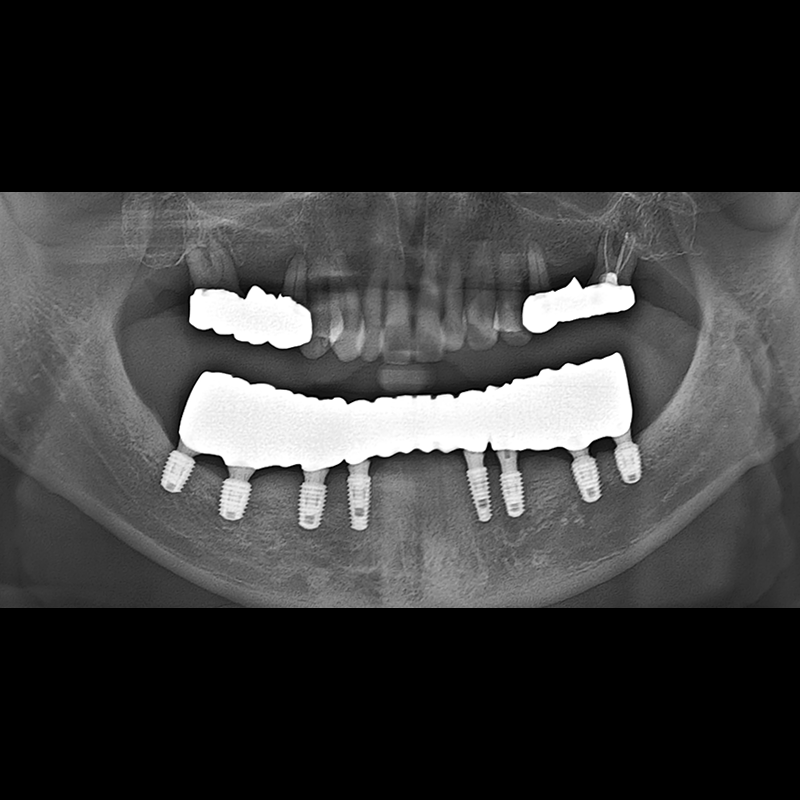

BEFORE AFTER

임플란트 전후사진 2025.05.30

결손된 치아 부분과 살리기 힘든 치아 위치에 임플란트를 식립하였습니다.